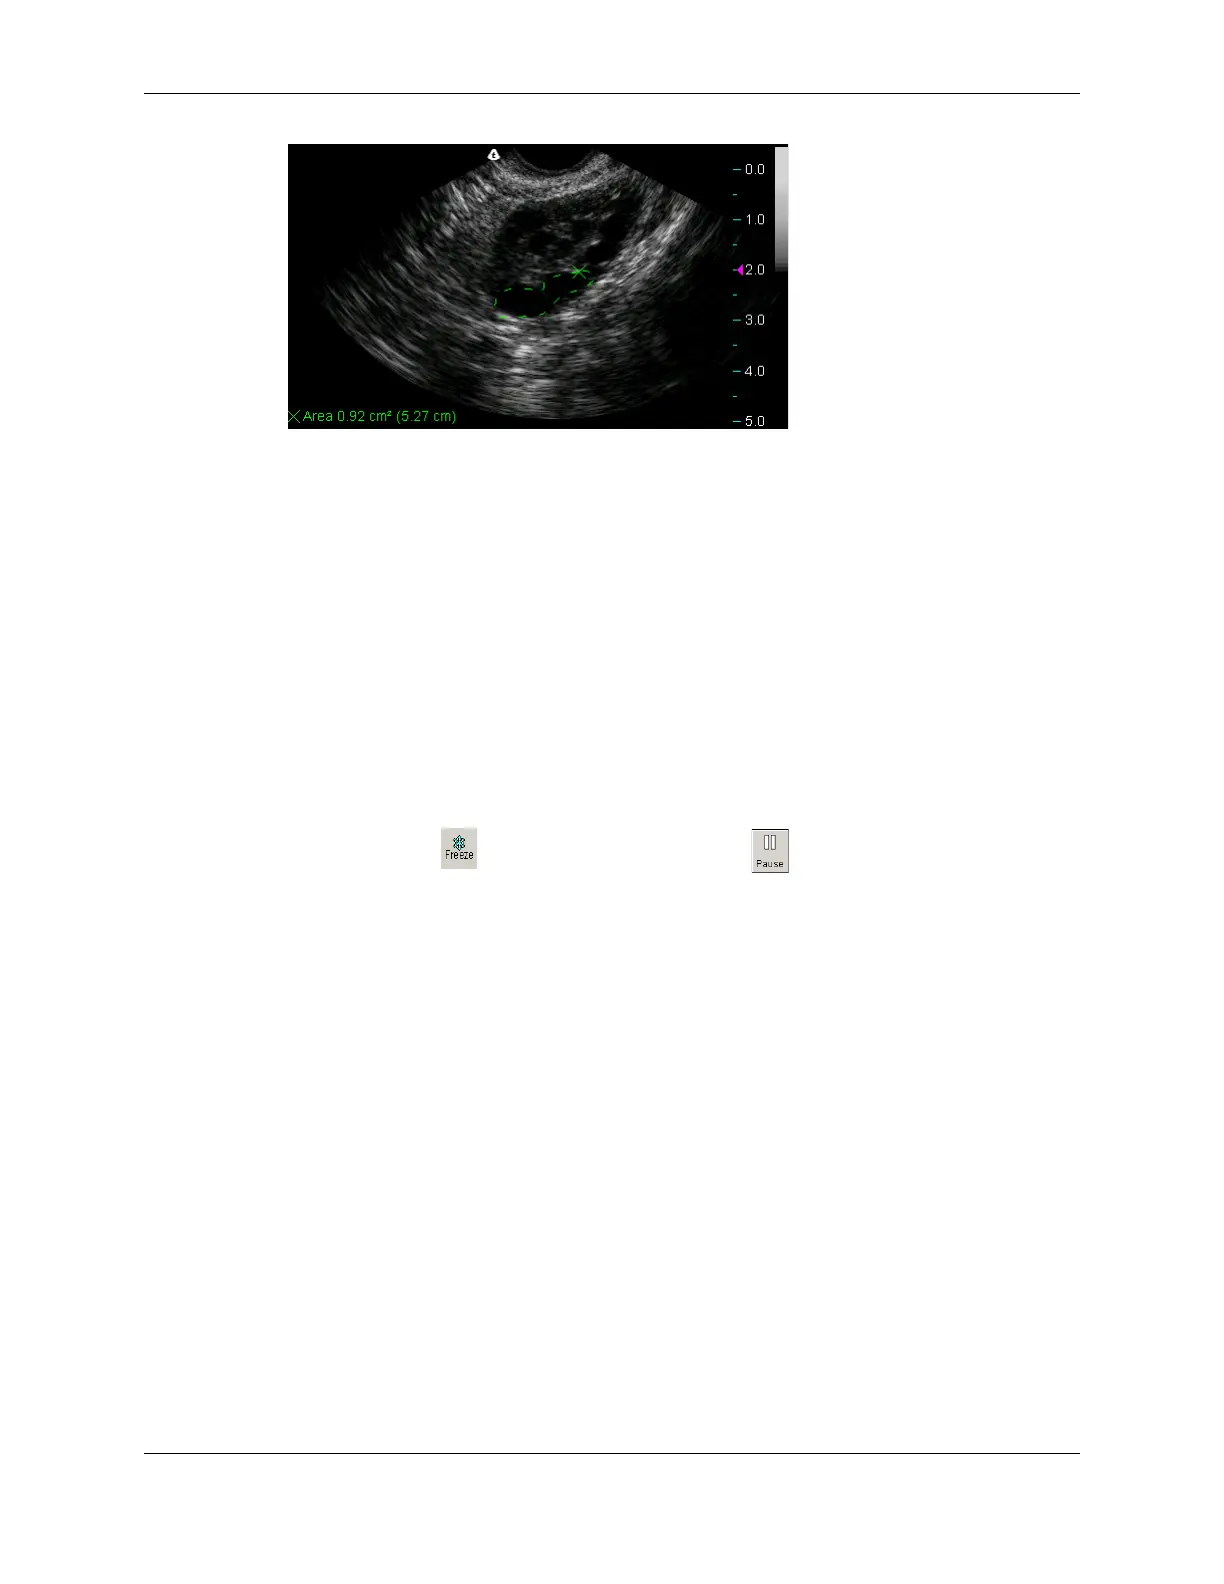

Trace Measurement on an Image

Calculating Percent Stenosis

If the 2D scan shows stenosis, you can measure the percent diameter or area stenosis

depending on the protocol in use.

To calculate the percentage, you must make two measurements: the full area or diameter

of the vessel and the residual lumen. When you complete the second measurement, the

Terason software calculates the percent of the area or diameter stenosis.